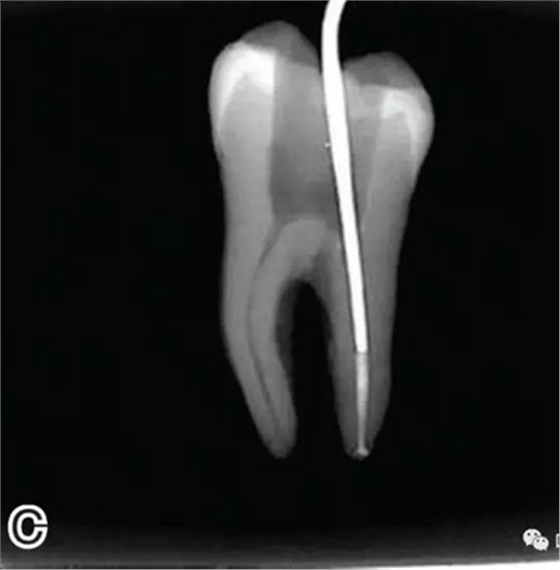

3、試尖

選擇非標(biāo)準(zhǔn)牙膠尖(如0.04、0.06 錐度牙膠尖)作為主尖,型號(hào)一般與根管預(yù)備最大號(hào)的器械型號(hào)一致,能到達(dá)距根尖0.5~1 mm 處,主尖尖段與根管壁緊密接觸。拍試尖X 線片進(jìn)行確認(rèn)(圖3)。

圖3 試尖,A.試主尖 B.拍試尖X片